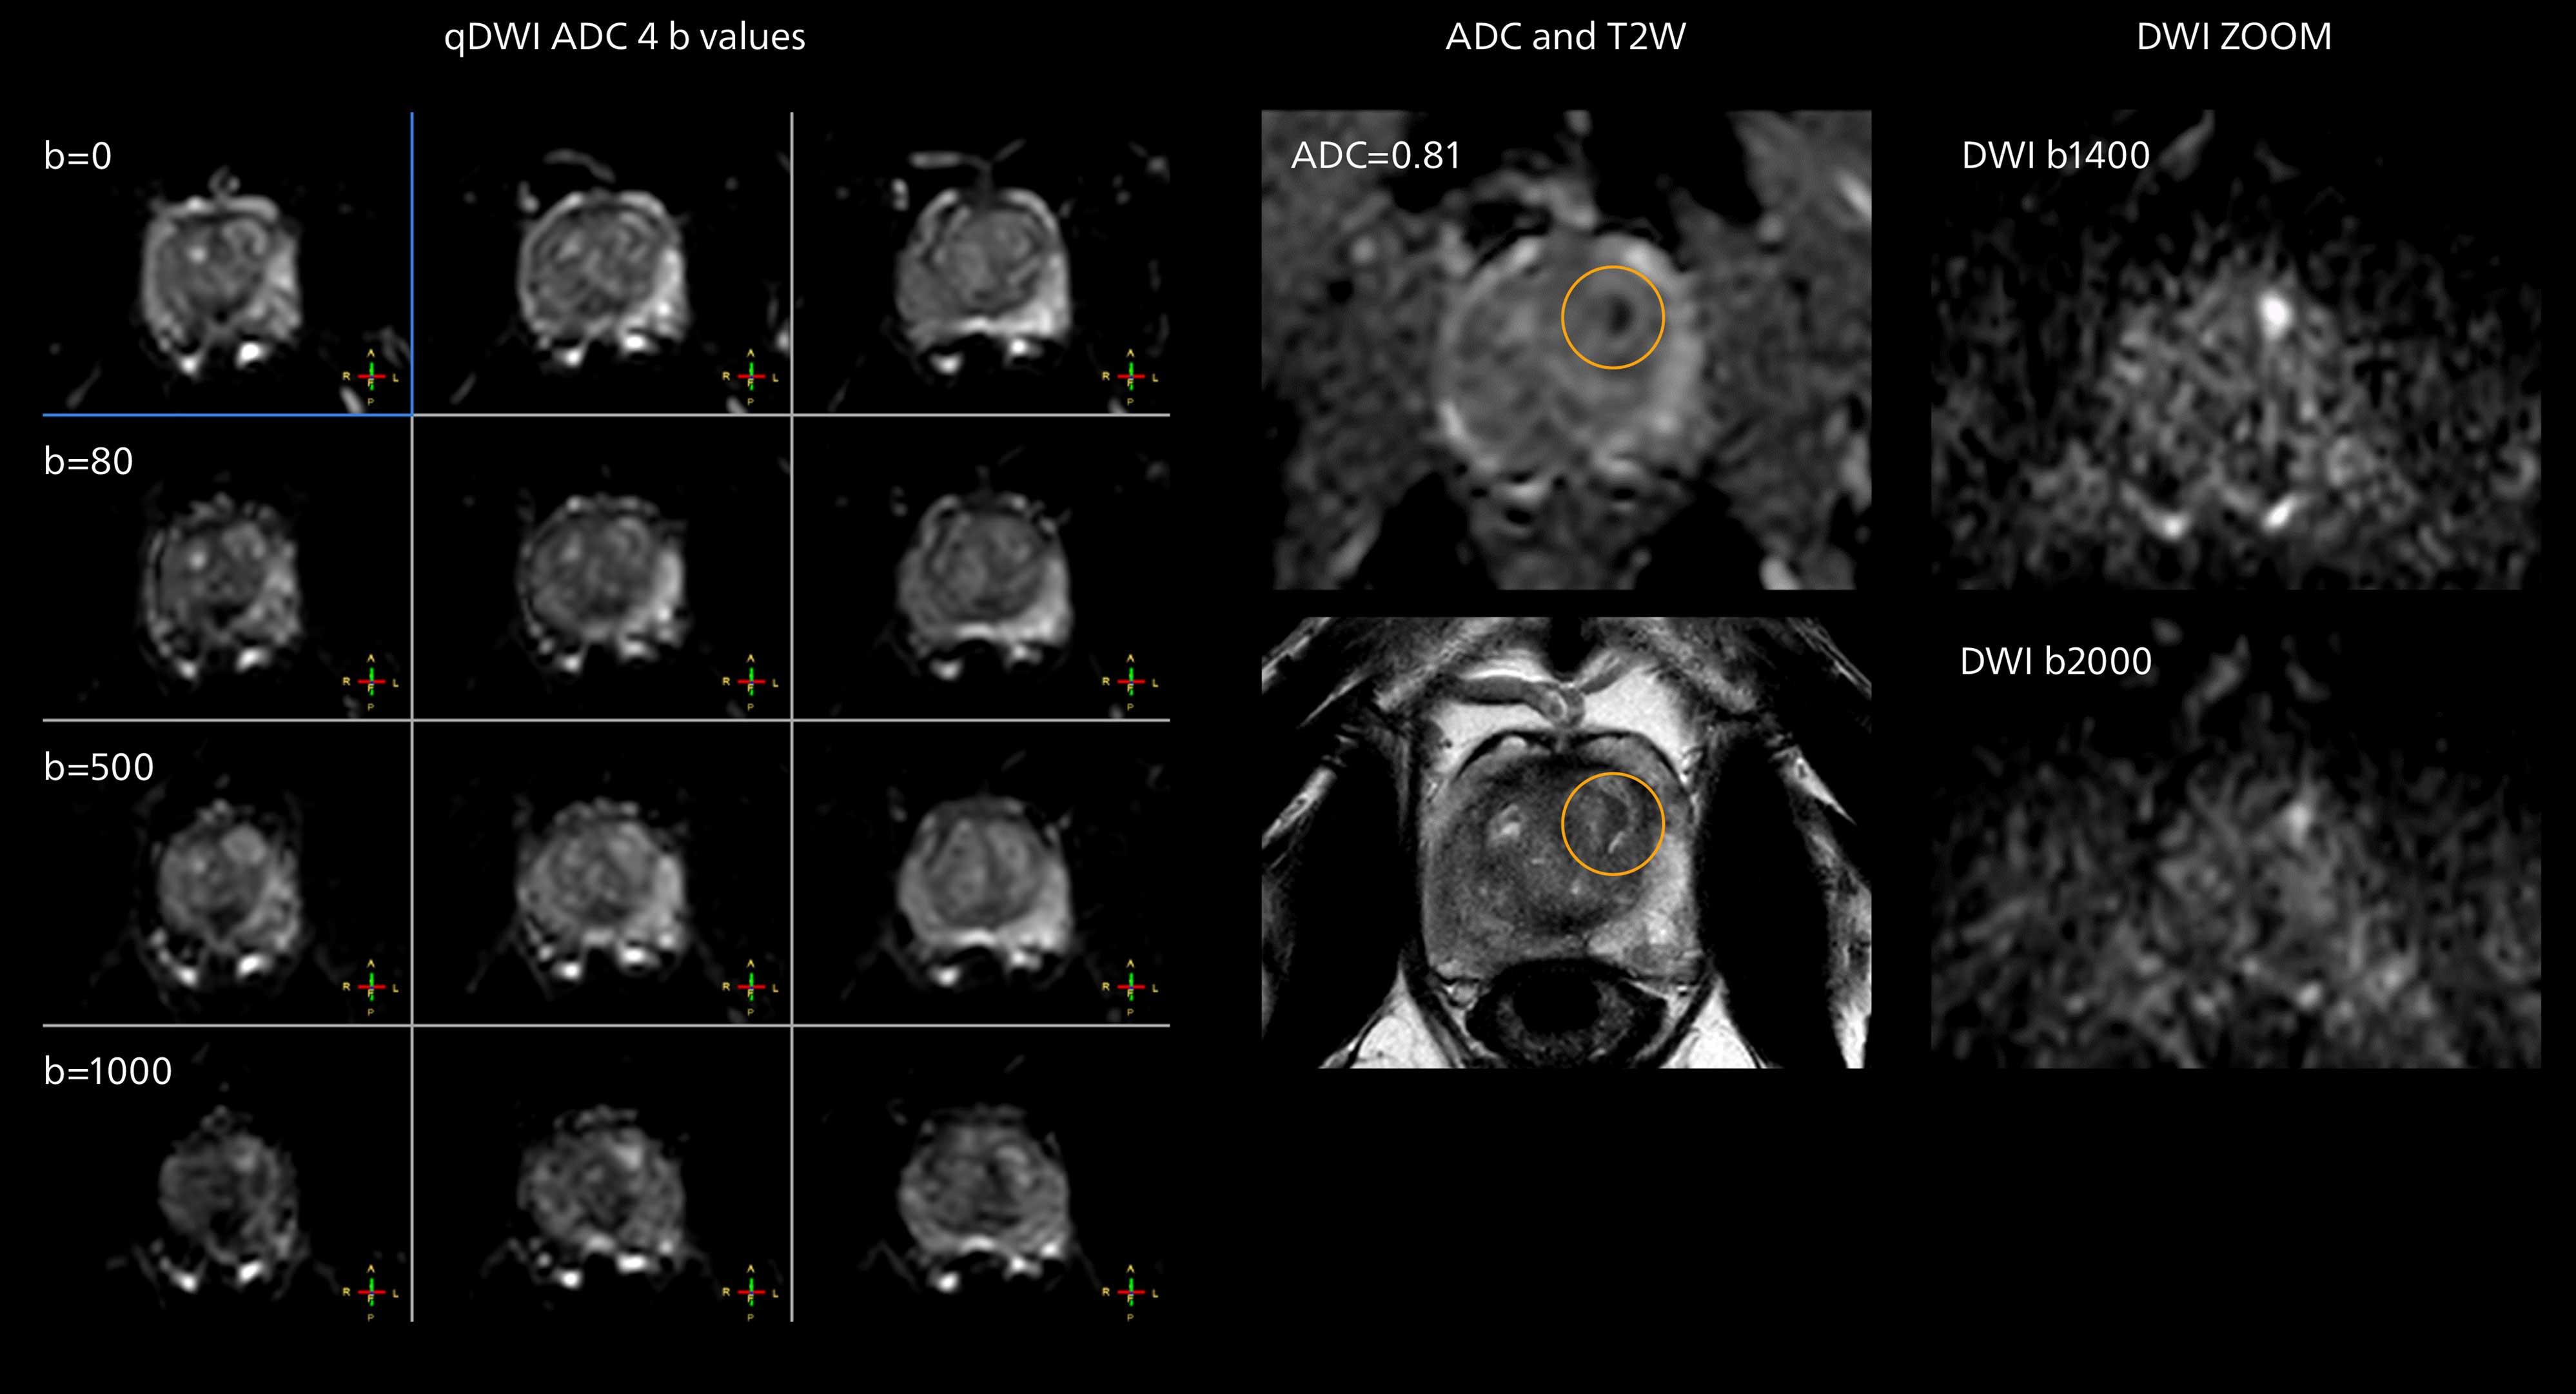

Diffusion weighted imaging of prostate

The examples on the left show the regular clinical diffusion protocol with four b-values up to b1000 s/mm². On the right, the T2W image shows a hypointense lesion that has low ADC and is clearly visible in b1400 and b2000 diffusion images, suggesting malignancy.

The prostate DWI done so far with the MR 7700 looks promising; the quality of visualizing the gland and the areas of disease seems significantly improved. “In one of our first prostate patients we were already able to acquire a quite high-resolution diffusion image – using a b-value of 3000 – that clearly delineated the prostate lesion. That was a very nice example of what the MR 7700 gradients can achieve,” he says.